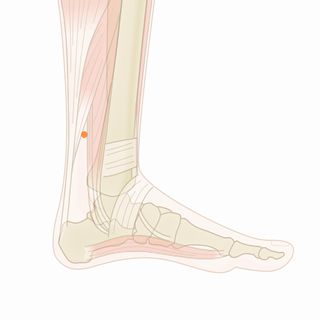

体の特徴を診ると、右頚部、右肩、背中のコリが強い。右目の症状とこれらのコリには深い関係があると判断した。 また、左足首の内側周辺に冷えが強いため、右上と左下でのバランスを調える必要性を感じた。右上と左下を意識した施術を行った。 1回目後、目の奥が気にならなくなったが、頚(後)と背中のコリが残った。 2回目後、症状はほぼ消失。施術を終了した。

使用したツボ